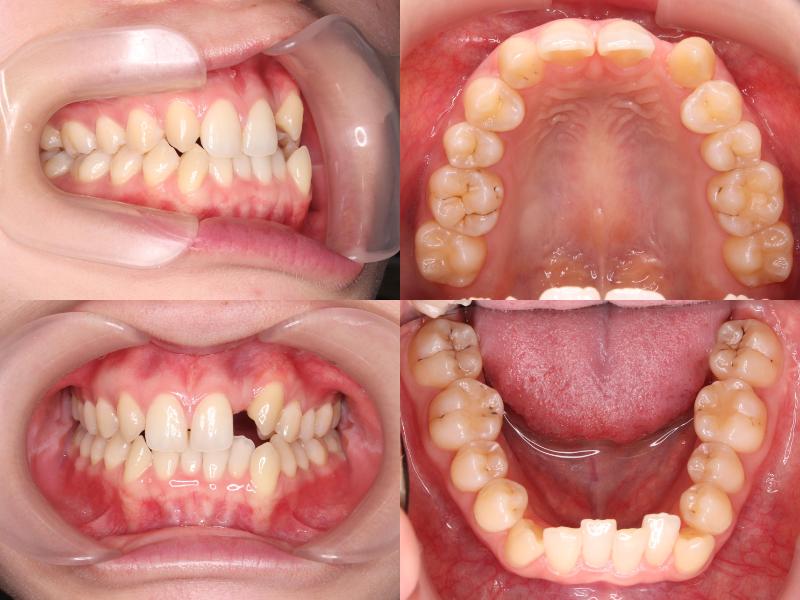

初診時年齢25歳1ヵ月の患者様です。

口元の突出感を主訴にご来院されました。

過蓋咬合と左上7番の根尖性歯周炎が認められたため、通常であれば上下左右4番を抜歯しますが、上下左右5番が処置歯であったため、5番を抜歯しました。